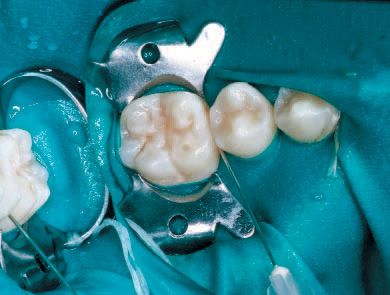

No local anesthesia is necessary, but rubber dam isolation is recommended to assist in the success of the ICON resin infiltration procedure. Cleanse the isolated tooth with NaOCl or Consepsis and rinse thoroughly with a water spray and air dry. The teeth are separated using one of the enclosed plastic wedges, which will allow for the placement of the Proximal-Tip foil matrix delivery system. The wedge can be maintained interproximally during the entire procedure if necessary (Fig. 5).

Screw one of the Proximal-Tips onto the end of the ICON-Etch (15% HCl), insert it between the teeth with the green side facing the affected proximal lesion, and turn the shaft 1½ to 2 turns to deliver the etchant. Leave the ICON-Etch on the surface for 2 minutes (Fig. 6).

No local anesthesia is necessary, but rubber

dam isolation is recommended to assist in the success

of the ICON resin infiltration procedure (Fig. 5).

Screw one of the Proximal-Tips onto the

end of the ICON -Etch (15% HCl), insert it between the

teeth with the green side facing the affected proximal

lesion, and turn the shaft 1 ½ to 2 turns to deliver

the etchant (Fig. 6).